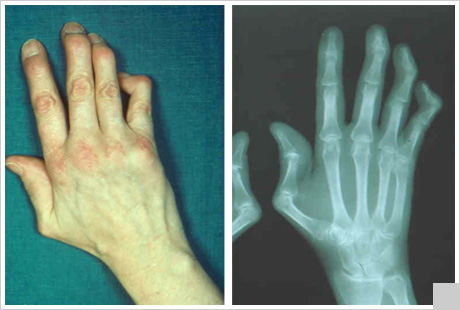

Поражение костно-суставной системы

Поражение костно-суставной системы проявляется следующими признаками:

• боли в одном или нескольких суставах интенсивные и длительные;

• симметричный полиартрит с вовлечением проксимальных межфаланговых суставов кистей, пятно-фаланговых, запястно-пястных, коленных суставов;

• выраженная утренняя скованность пораженных суставов;

• развитие сгибательных контрактур пальцев рук вследствие тендинитов, тендовагинитов;

• формирование ревматоидноподобной кисти за счет изменений в периартикулярных тканях; эрозии суставных поверхностей нехарактерны (могут быть лишь у 5% больных);

• возможно развитие асептических некрозов головки бедренной кости, плечевой и других костей.

Могут возникать большие трудности при дифференциальной диагностике суставного синдрома при системной красной волчанке и поражений суставов при ревматоидном артрите.

9. Рентгенография суставов: эпифизарный остеопороз преимущественно в суставах кистей, реже - в запястно-пястных и лучезапястных суставах, истончение субхондральных пластинок, мелкие узуры суставных костей (лишь в 1-5% случаев) с подвывихами.